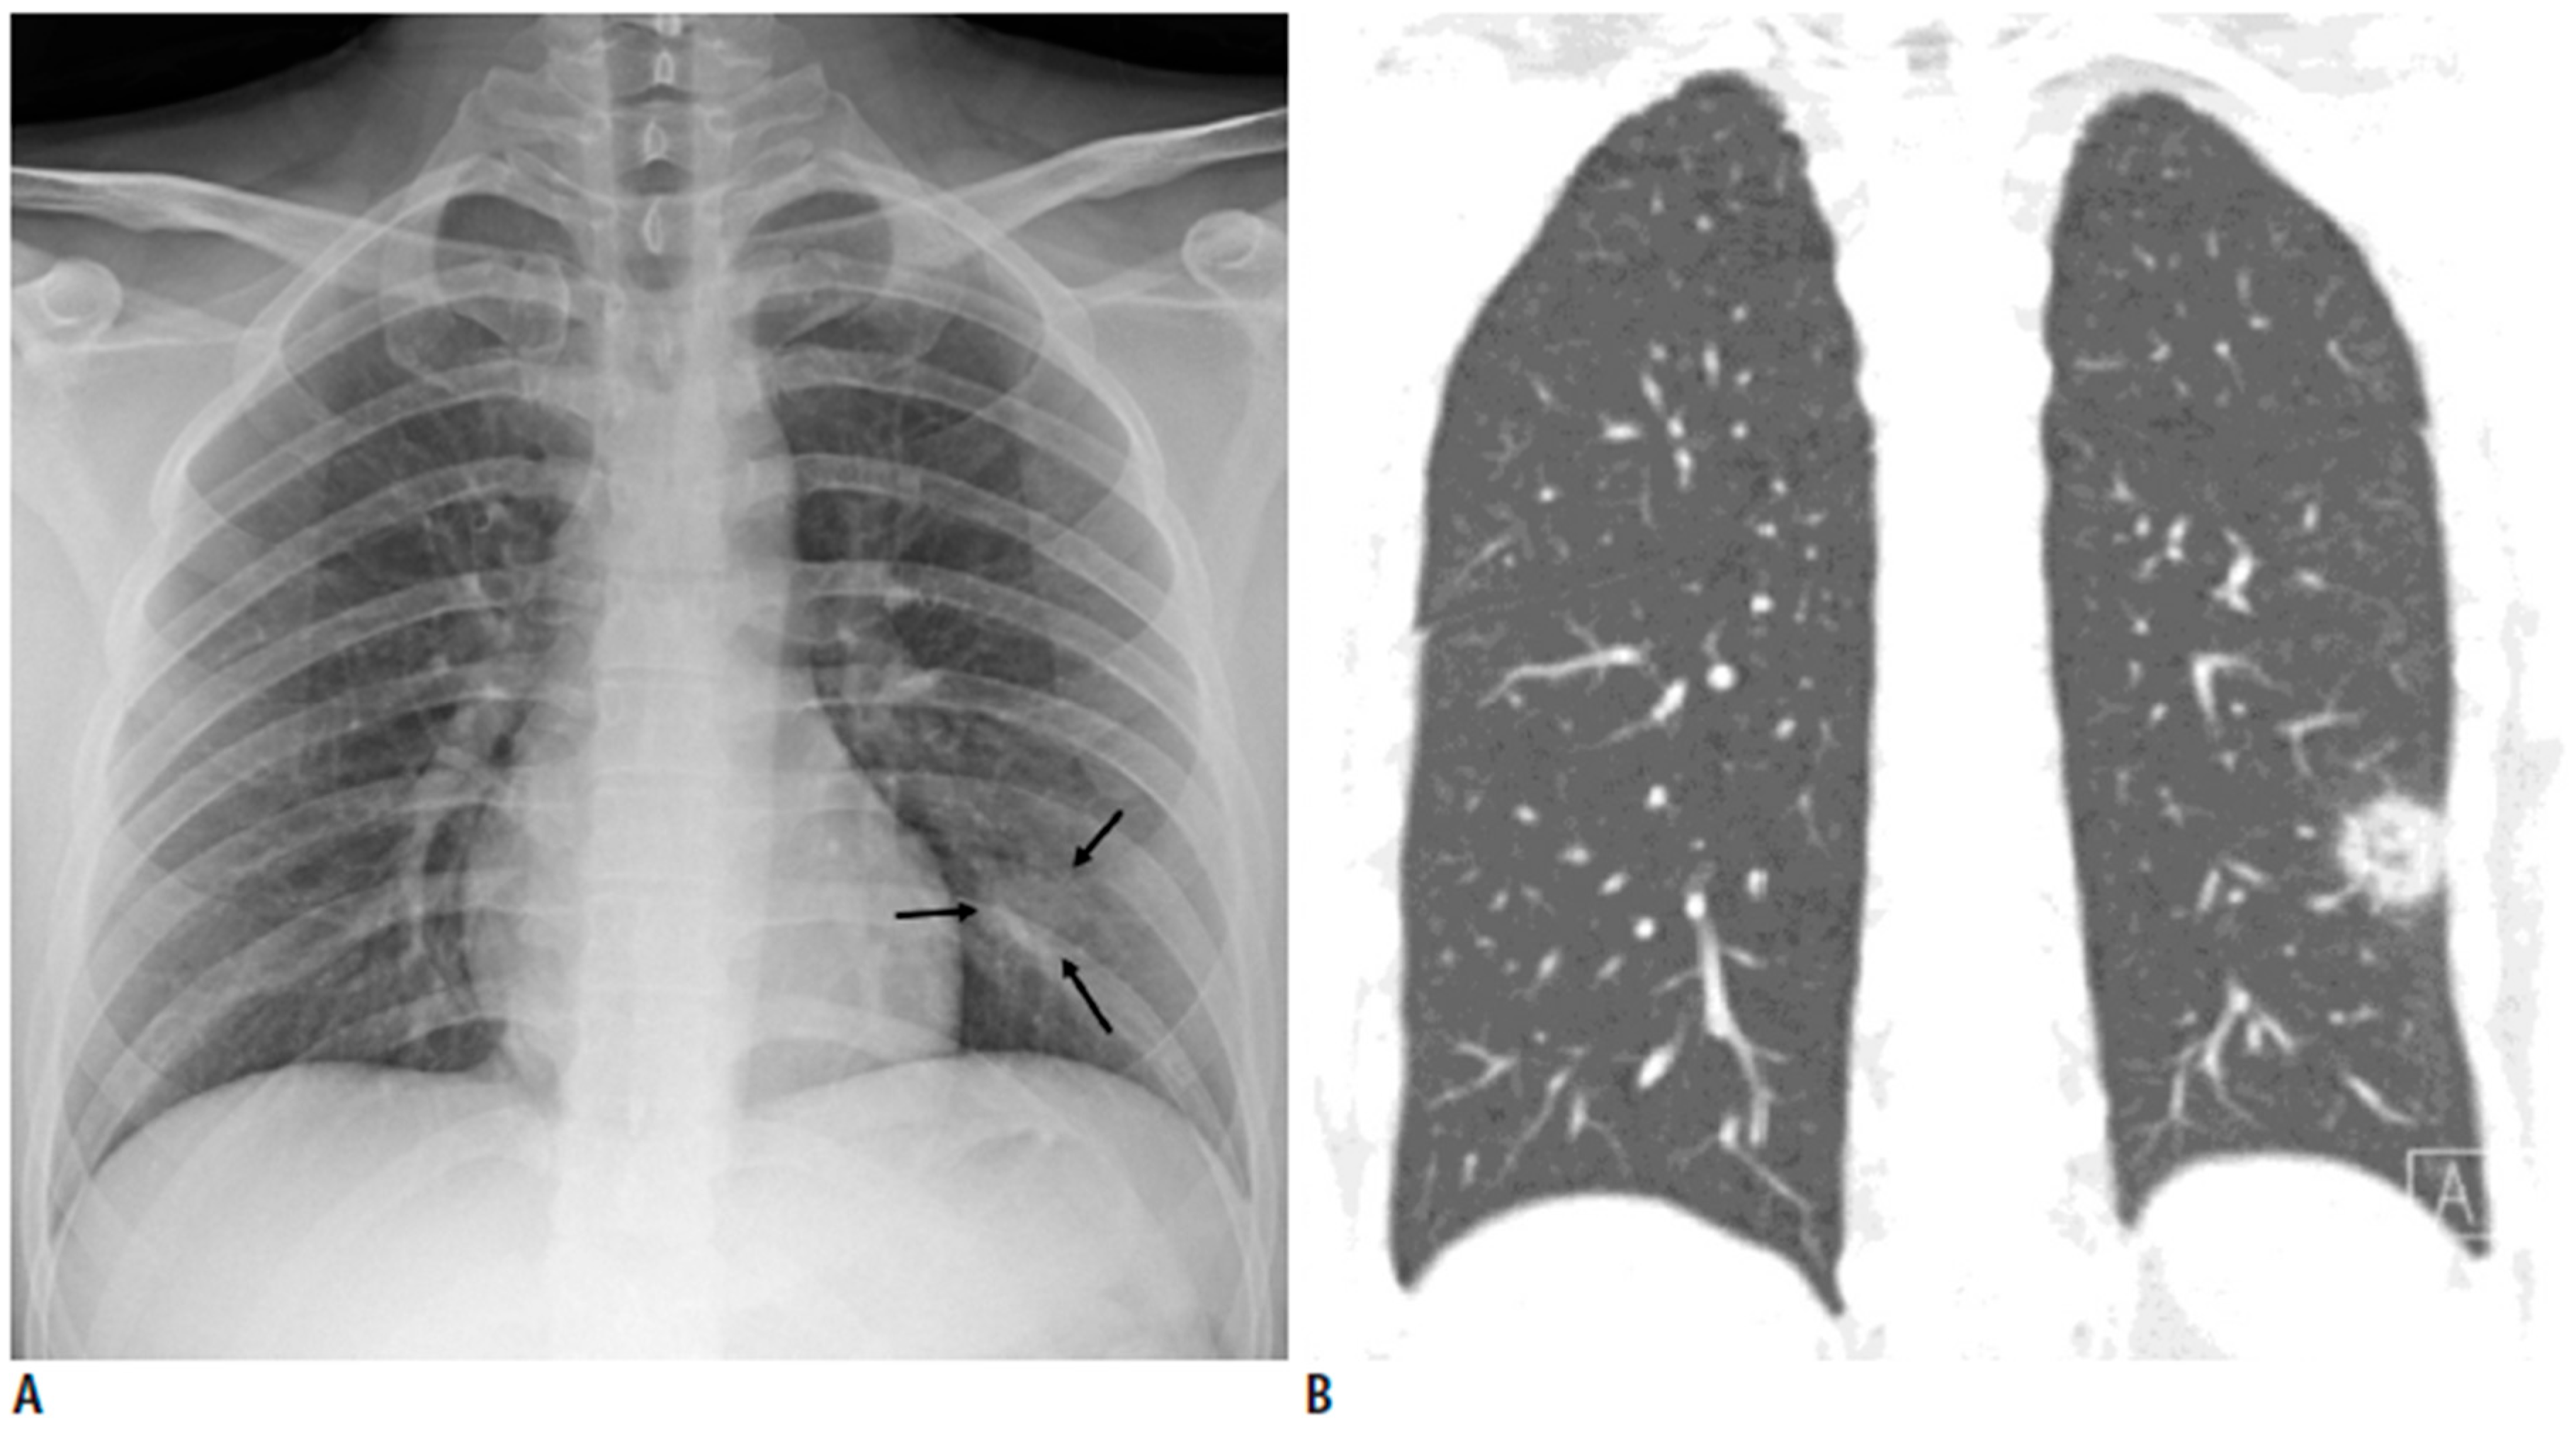

3.2. Case B